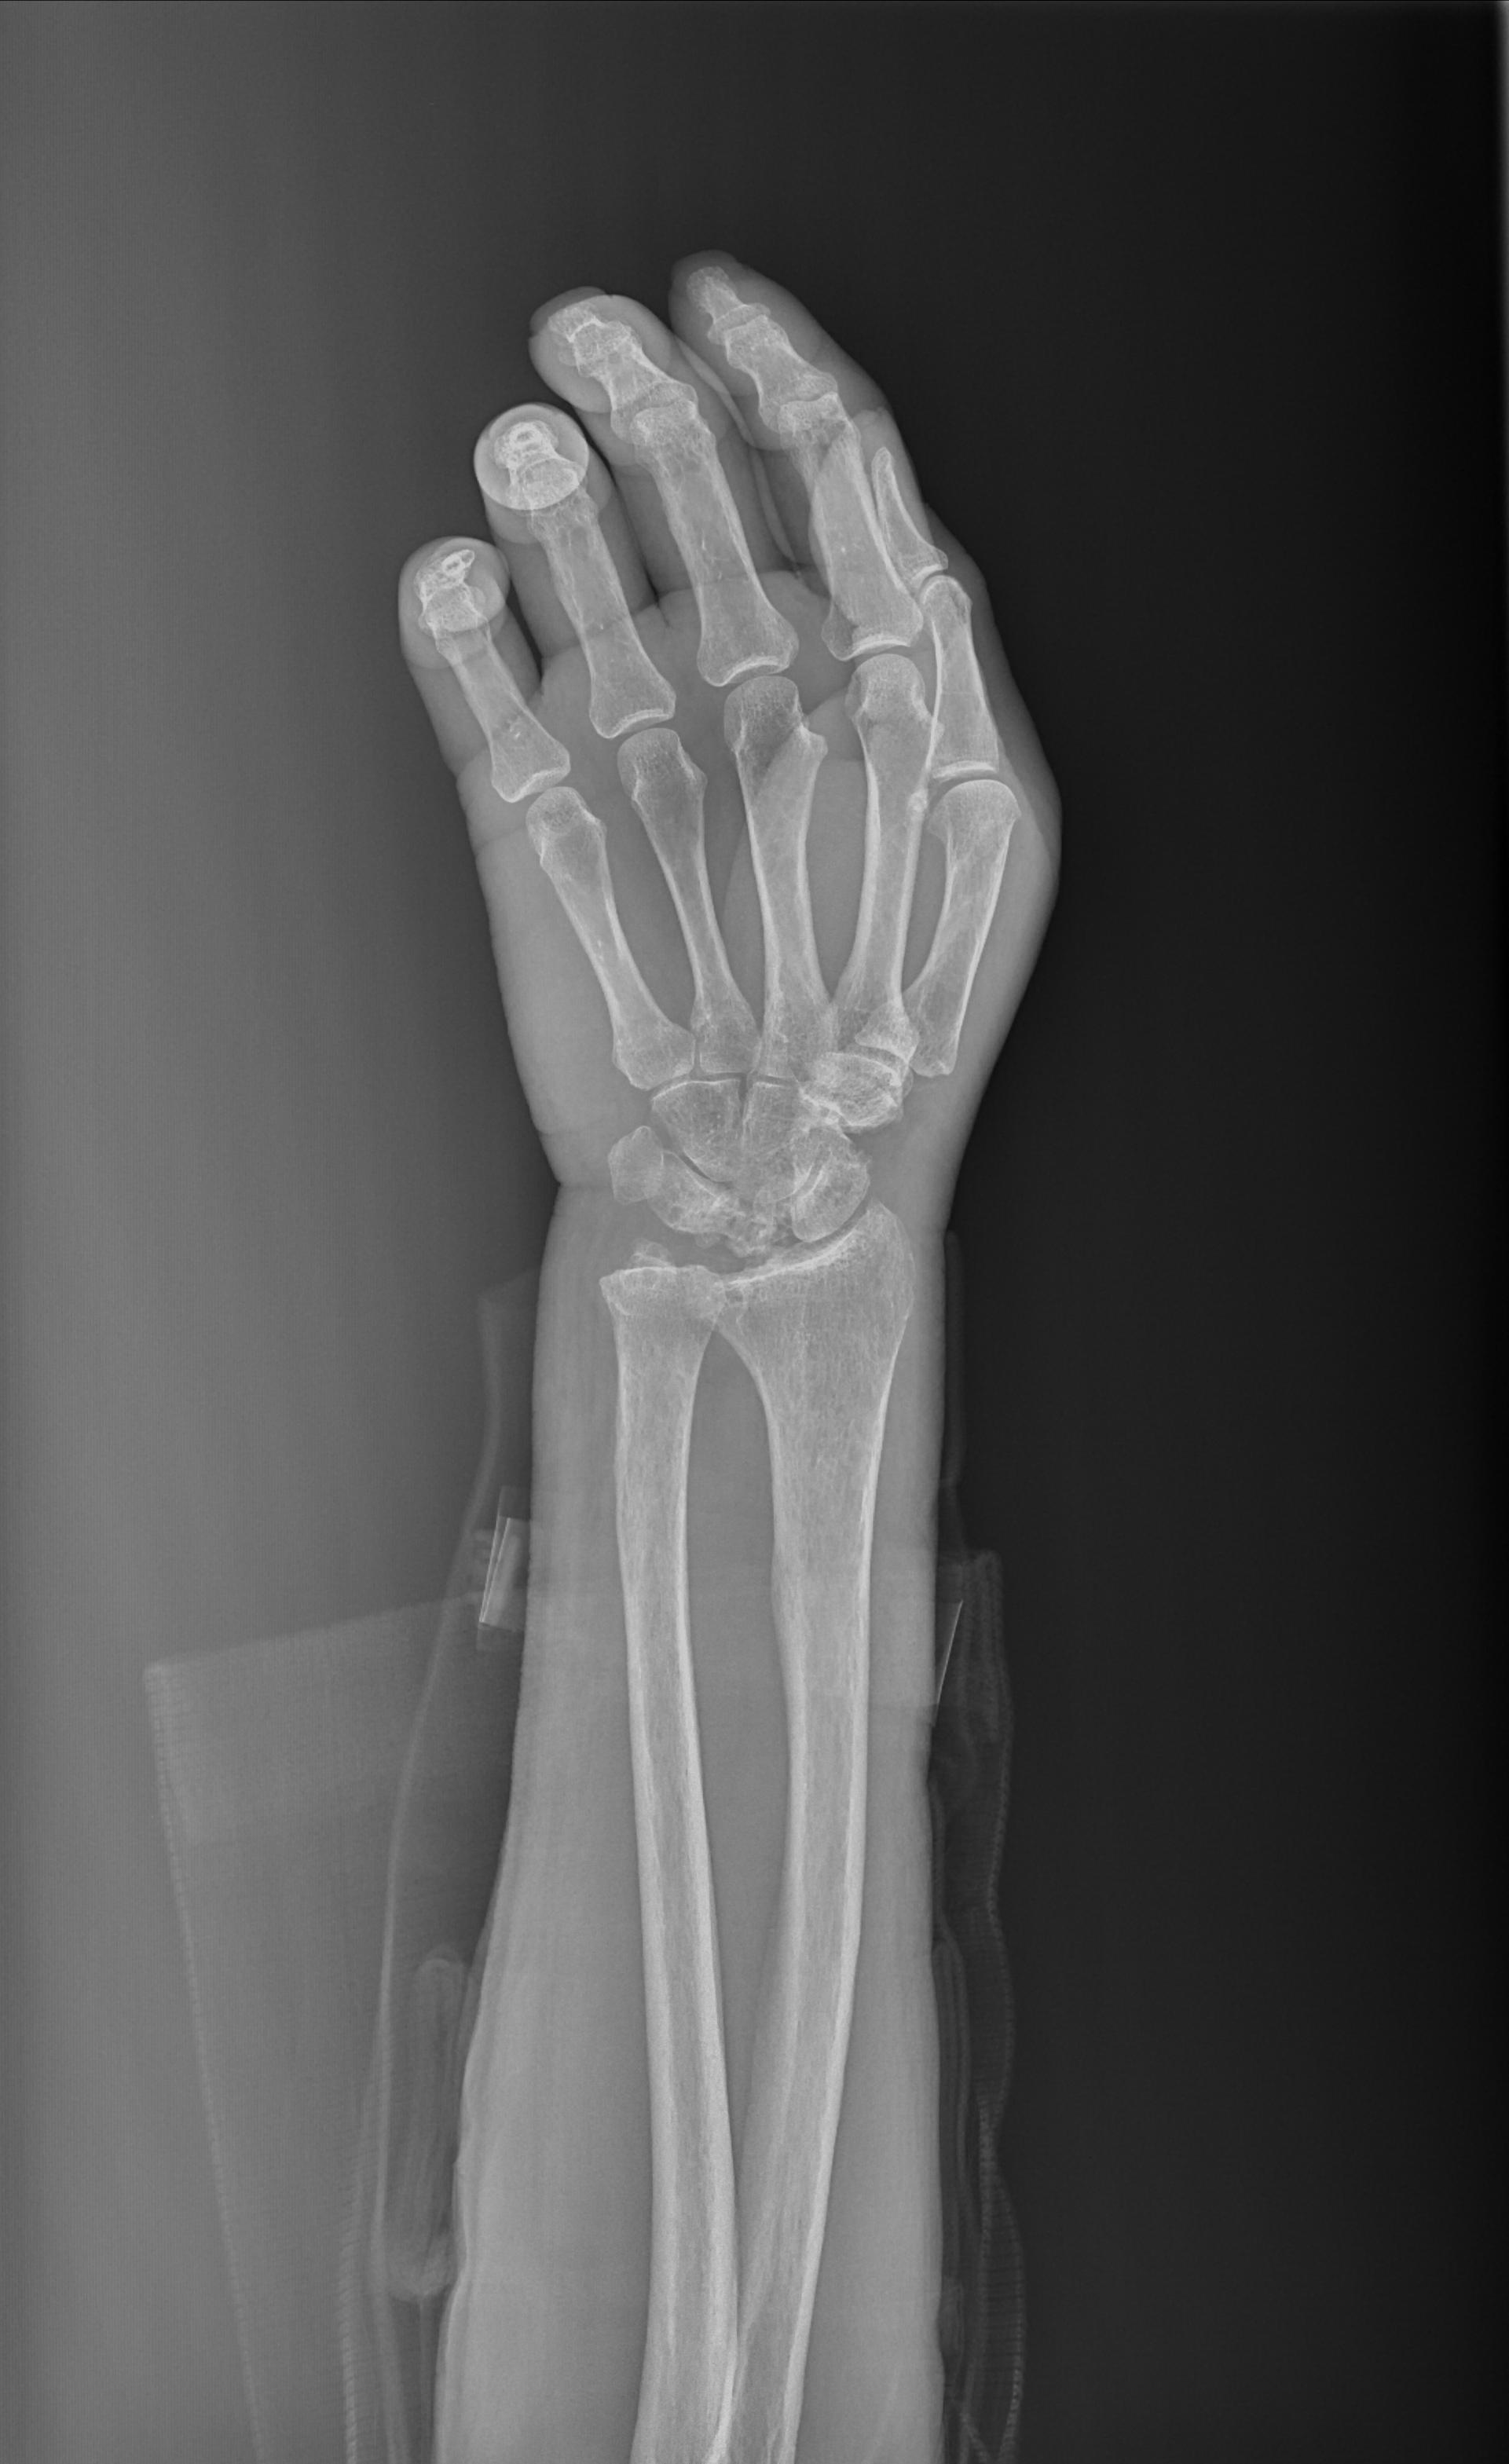

X14140:右腕关节

女,77岁,因腕部受伤拍片,掌背软组织肿胀,此前手腕活动良好。

右侧月骨、三角骨骨质密度不均,部分囊变,月骨尤著且体积缩小。考虑:右侧月骨及三角骨缺血性坏死,尺骨撞击综合征?

右侧尺骨撞击综合征;右侧月骨及右侧三角骨缺血性坏死。